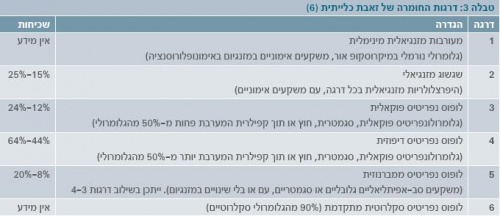

ארגון הבריאות העולמי (WHO - World Health Organization) הגדיר סיווג מורפולוגי המבוסס על ביופסיה כלייתית (תמונה 1), שעודכן בשנת 2003 על ידי החברה הבין-לאומית לנפרולוגיה ופתולוגיה כלייתית[6]. טווח הסיווג ההיסטולוגי הוא מכליה נורמלית במיקרוסקופ אור (דרגה 1) עד דלקת כליה טרשתית מתקדמת (דרגה 6) (טבלה 3).

- דרגה 1 - ללא טיפול.

- דרגה 2 - קורס קצר של סטרואידים במינון נמוך (0.1-0.5 מ"ג לק"ג Prednisone ביום), עם הפחתה הדרגתית במהלך מספר חודשים. הפרוגנוזה של חולים אלו מצוינת.

- דרגות 4-3 - קורס ארוך של סטרואידים במינון גבוה (2 מ"ג לק"ג Prednisone ליום, עד מקסימום 80-60 מ"ג ביום, במנות מחולקות). לרוב מוסיפים טיפול נוסף, כגון פעימה (Pulse) חודשיים של Endoxan (Cyclophosphamide) או טיפול יומי ב-Azathioprine. ייתכן שגם Mycophenolate mofetil יכול להיות אפקטיבי, כמו Endoxan. Mycophenolate mofetil ו-Azathioprine בטוחים יותר לשימוש מ-Endoxan.

- דרגה 5 - רוב החולים בדרגה 5 נדרשים לקורסים קצרים של סטרואידים במינון נמוך. רק מיעוטם נדרש לקורס ארוך או לשימוש בטיפול נוסף.